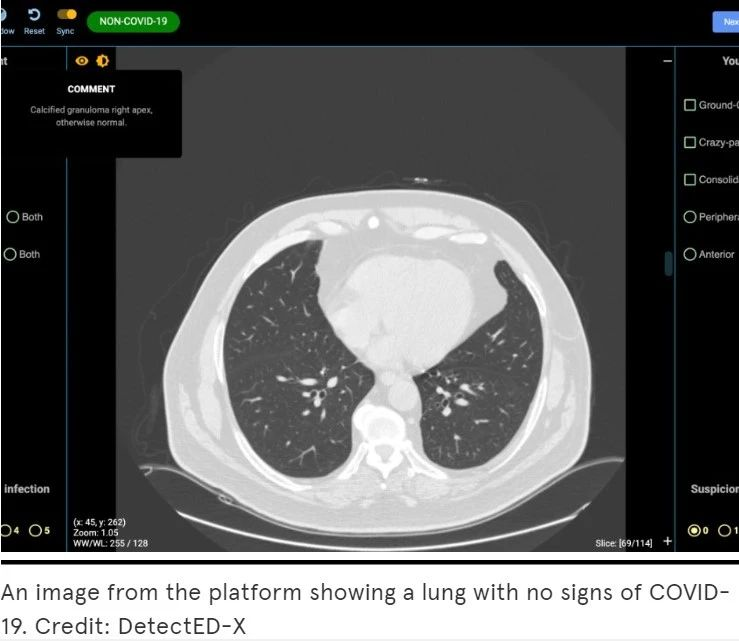

尽早诊断新型冠状肺炎对早期治疗和隔离至关重要。目前,肺部CT已被证明是诊断新型冠状肺炎的首要工具,但医生的CT读片技能可能需要长年累月的经验积累。由DetectED-X开发的名为CovED的辅助测试工具将帮助现有的医生及相关工作人员更快、更准确地诊断病例,并为更多有需要的人员及机构提供快速培训,从而获得完备的CT读片技能,其定制化的培训模块只需要1-2小时就可以生成。

CovED是一个全网开放且免费的平台,得到了全球医疗专家和领先企业的支持。借助CovED,临床医生可以通过真实的CT图像进行虚拟诊断并得到即时的反馈,查看虚拟诊断中产生的所有错误。系统还会按照业界标准为其打分,以此帮助使用者评估自身表现。随着时间的推移,诊断难度也会相应增加。

未感染COVID-19 CT图